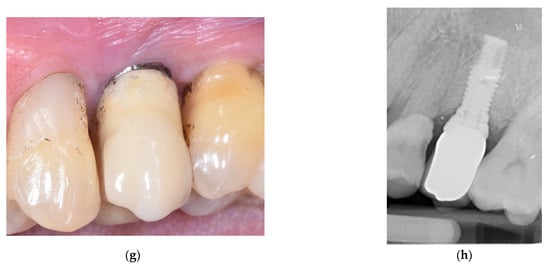

2. Materials and Methods

3. Results

- Bianchini, M.A.; Galarraga-Vinueza, M.E.; Bedoya, K.A.; Correa, B.B.; de Souza Magini, R.; Schwarz, F. Implantoplasty Enhancing Peri-implant Bone Stability Over a 3-Year Follow-up: A Case Series. Int. J. Periodontics Restor. Dent. 2020, 40, e1–e8. [Google Scholar] [CrossRef]

- Bianchini, M.A.; Galarraga-Vinueza, M.E.; Apaza-Bedoya, K.; De Souza, J.M.; Magini, R.; Schwarz, F. Two to six-year disease resolution and marginal bone stability rates of a modified resective-implantoplasty therapy in 32 peri-implantitis cases. Clin. Implant. Dent. Relat. Res. 2019, 21, 758–765. [Google Scholar] [CrossRef] [PubMed]

- Suh, J.J.; Simon, Z.; Jeon, Y.S.; Choi, B.G.; Kim, C.K. The use of implantoplasty and guided bone regeneration in the treatment of peri-implantitis: Two case reports. Implant Dent. 2003, 12, 277–282. [Google Scholar] [CrossRef] [PubMed]

- Austoni, C.; Azzola, F.; Cavalli, N.; Morandi, P.; Francetti, L. Implantoplasty associated with the regenerative treatment of peri-implantitis. Dent. Cadmos 2019, 87, 262–269. [Google Scholar] [CrossRef]